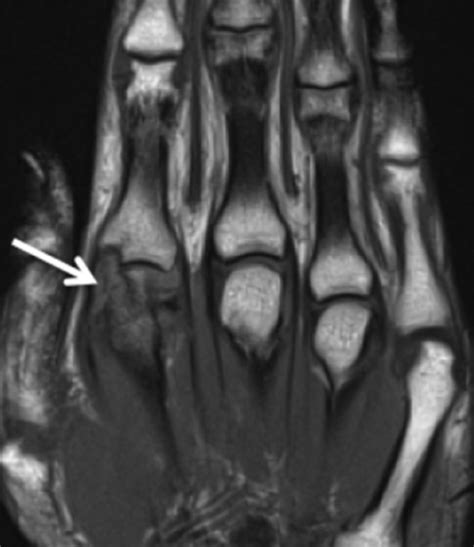

Finger Fractures - OrthoInfo - AAOS